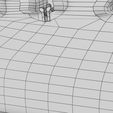

神经肌肉接头示意图